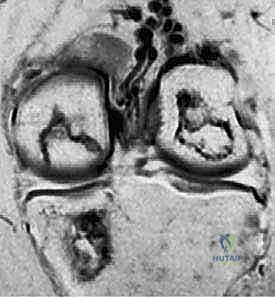

3. التصوير بالرنين المغناطيسي (MRI) – المعيار الذهبي

لا يمكن تقييم الغضروف المفصلي بدقة باستخدام الأشعة السينية. هنا يأتي دور الرنين المغناطيسي العالي الدقة. يُعد الرنين المغناطيسي حجر الزاوية في خطة الأستاذ الدكتور محمد هطيف التشخيصية، حيث يسمح بـ:

* تقييم حالة الغضروف المفصلي (هل هو سليم، متورم، أم ممزق؟).

* تحديد مدى ثبات القطعة العظمية (في حالات OCD). وجود سائل بين القطعة والسرير العظمي في صور T2 يشير إلى عدم الاستقرار.

* اكتشاف الوذمة العظمية (Bone Marrow Edema) التي تميز حالات SONK و AVN في مراحلها المبكرة قبل ظهورها في الأشعة السينية.

* تحديد حجم وعمق الآفة بدقة مليمترية للتخطيط الجراحي.